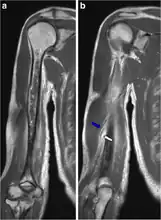

X-ray pneumococcal osteomyelitis

MRI pneumococcal osteomyelitis